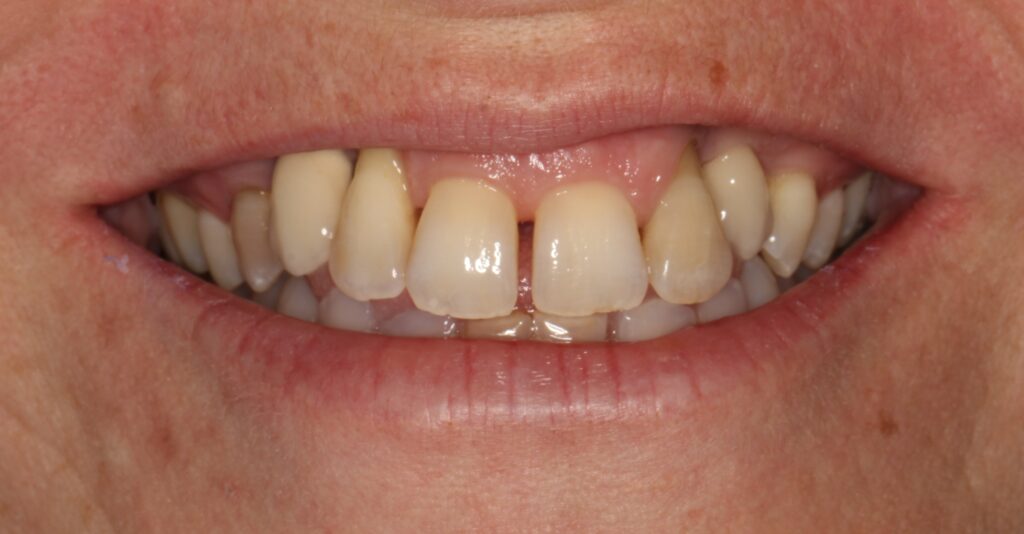

A selection of partial arch fixed implant bridge patients